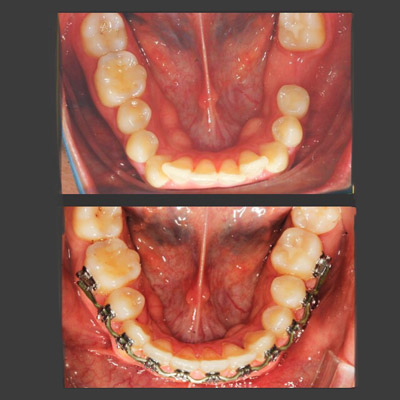

img

La paciente llegó a la consulta referida por el otorrinolaringólogo por presentar problemas para respirar. Su caso era de una protrusión excesiva, teniendo también problemas de autoestima por su apariencia física. Después de realizar el tratamiento puede respirar mejor y se siente feliz.